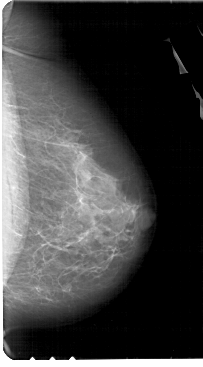

A_1945_1.LEFT_MLO

LEFT_MLO LINES 5491 PIXELS_PER_LINE 3391 BITS_PER_PIXEL 12 RESOLUTION 43.5 OVERLAY

FILE: A_1945_1.LEFT_MLO.OVERLAY

TOTAL_ABNORMALITIES 1

ABNORMALITY 1

LESION_TYPE CALCIFICATION TYPE PLEOMORPHIC DISTRIBUTION CLUSTERED

ASSESSMENT 4

SUBTLETY 2

PATHOLOGY BENIGN

TOTAL_OUTLINES 1

BOUNDARY